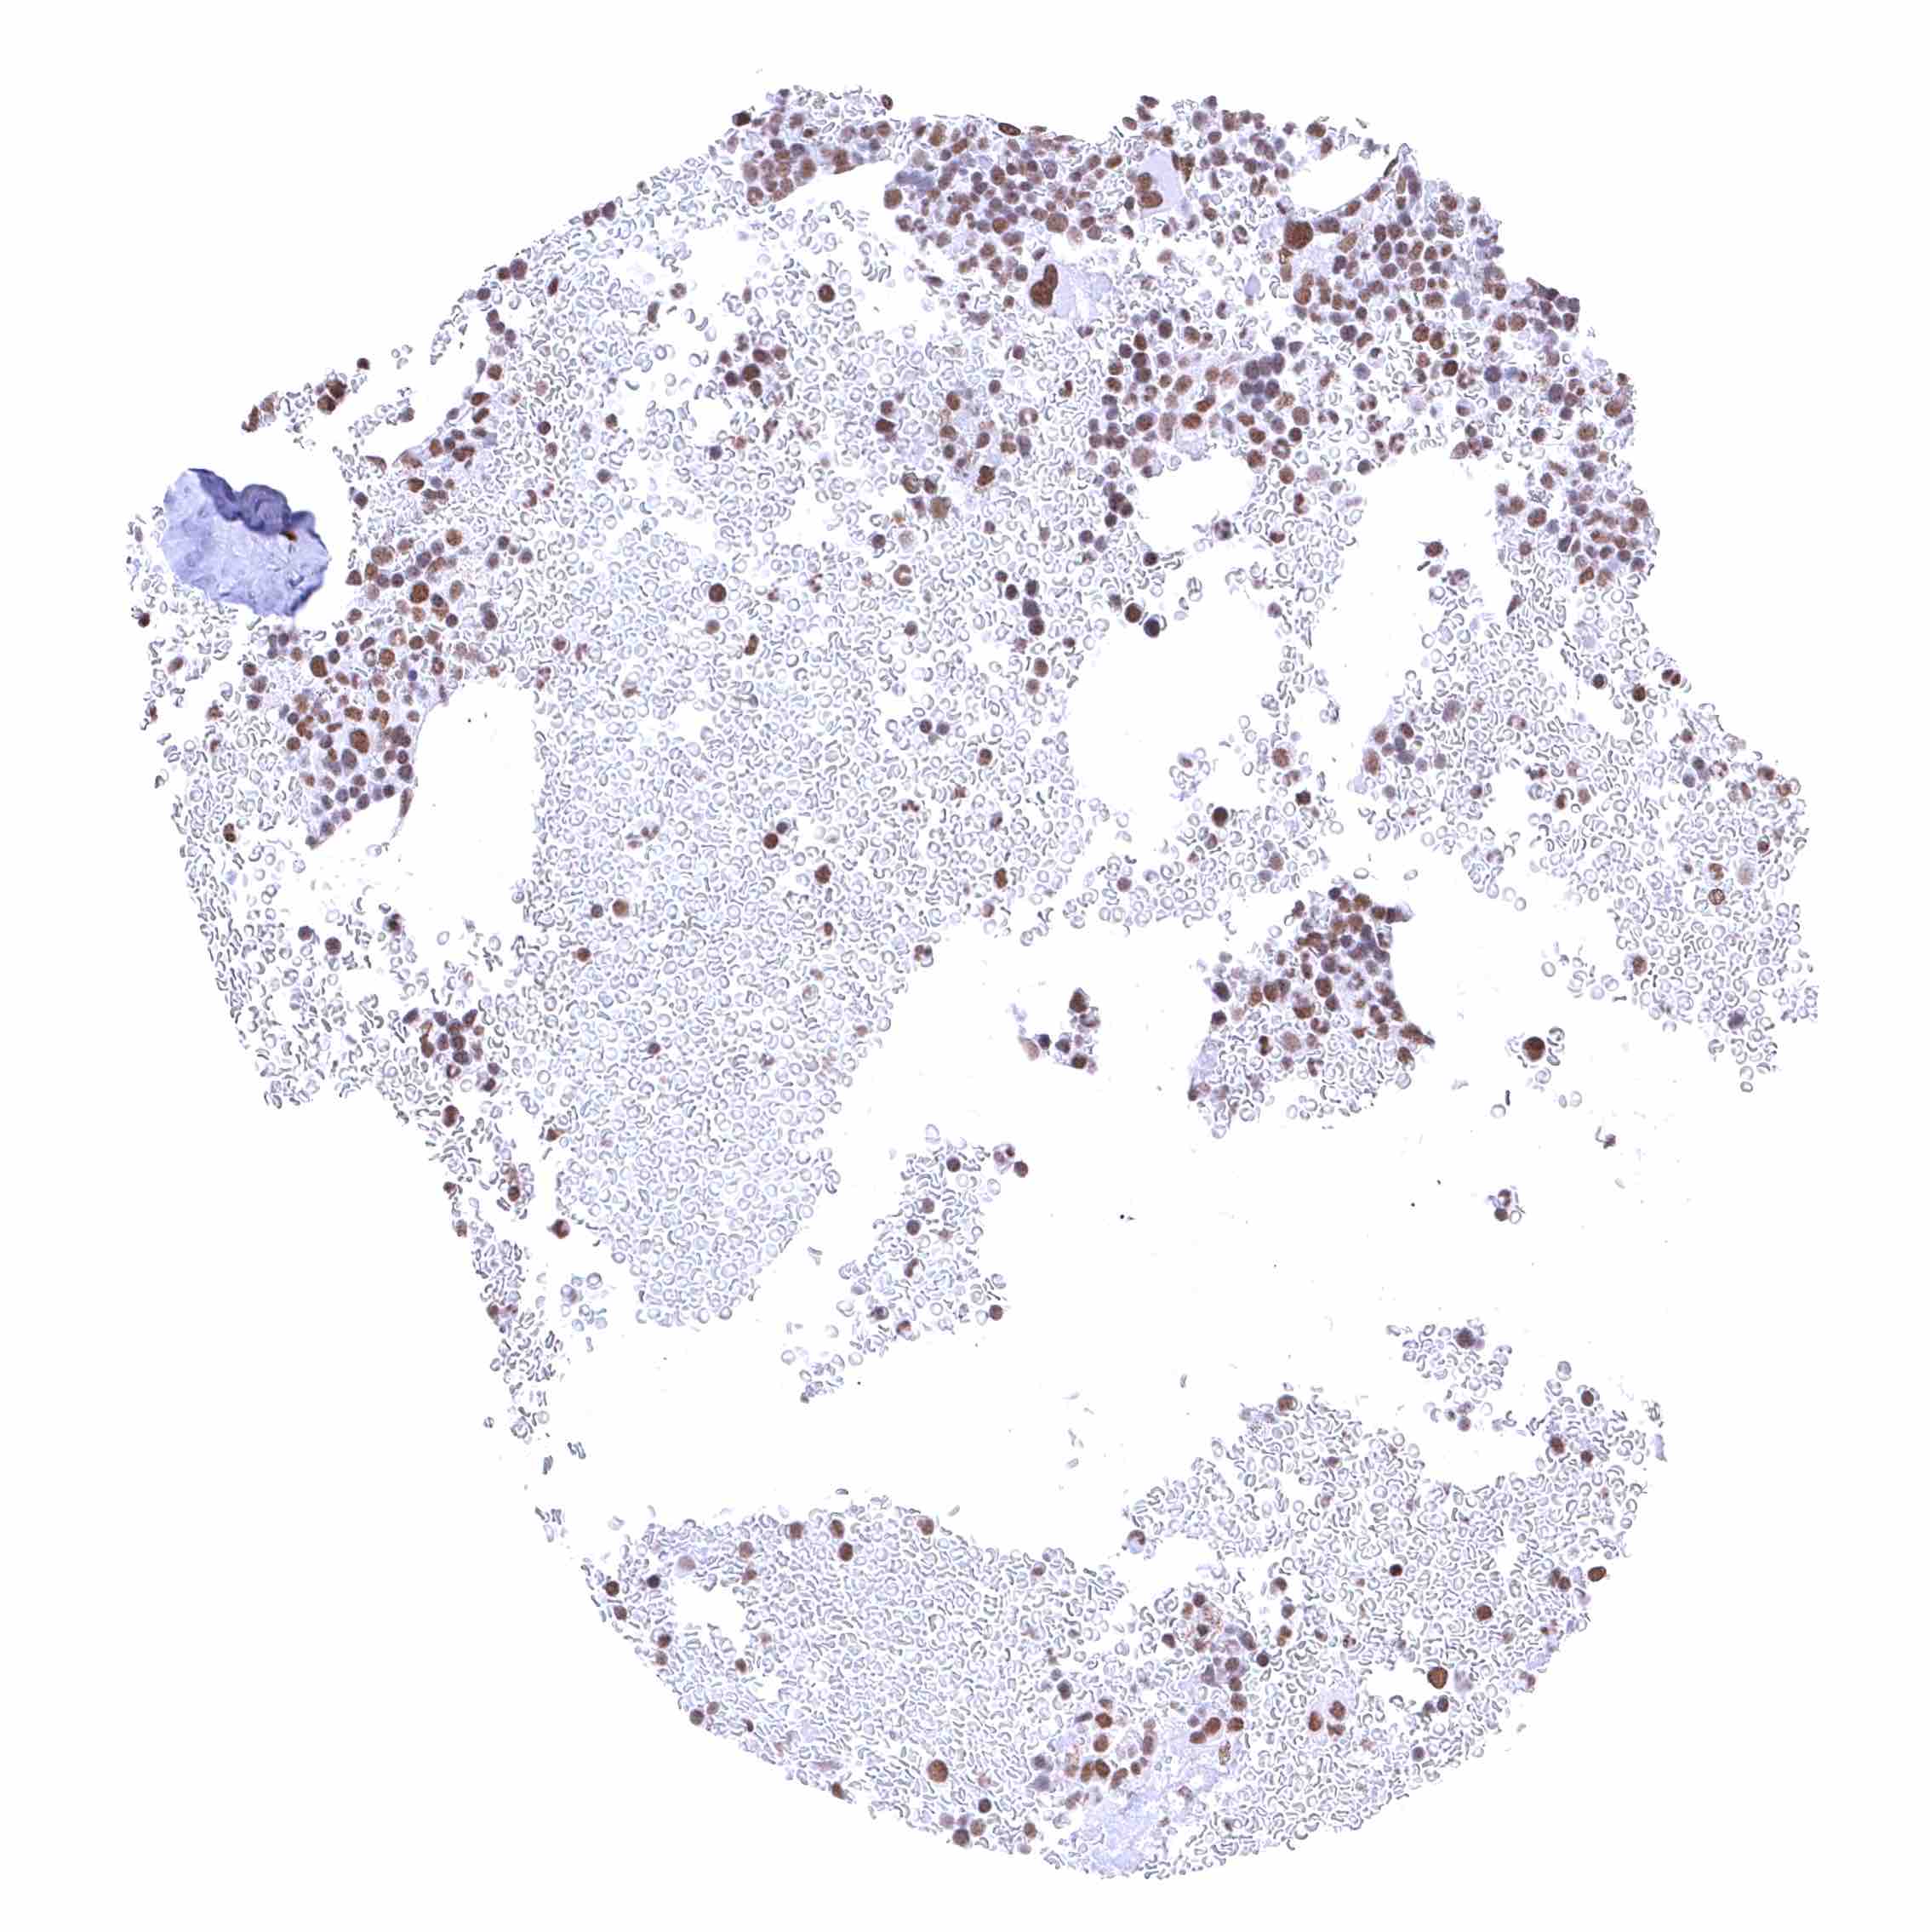

Tonsil – Strong nuclear BRD4 staining of all cell types.

Tonsil, surface epithelium